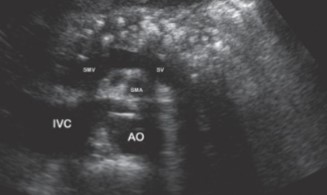

This image was taken in what plane?

Explain your answer.

Transverse

The entire pancreas is visualized